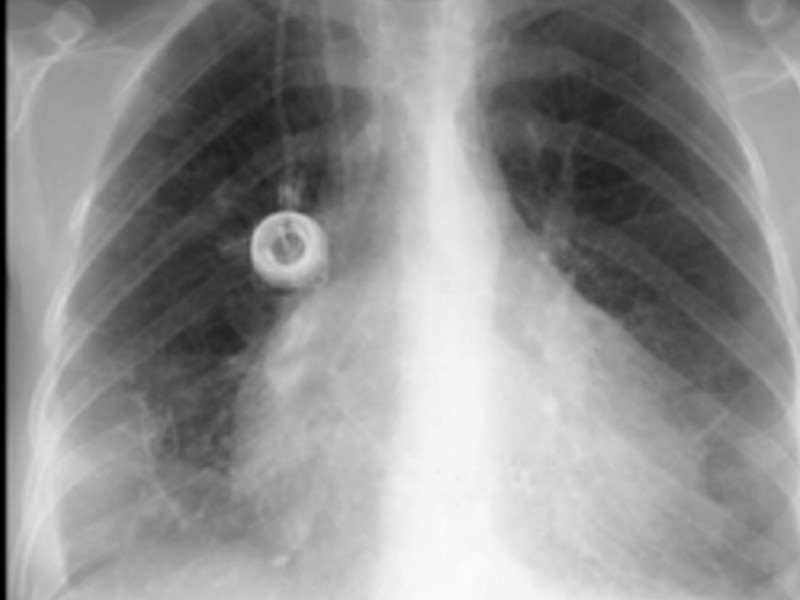

Ушиб легких Потенциально жизнеугрожающее состояние с коварным началом Повреждение паренхимы без разрывов Более чем 50% будет развиваться пневмония, даже с лечением До 50% имеют только кровавую мокроту как представляющий симптом

Ушиб легких Пациенты с сопутствующими состояниями нуждаются в ранней интубации ХОЗЛ, астма, эмфизема Нарушение уровня сознания Непроходимость от повреждения живота, диагностическая лапаратомия Иммобилизация переломов Почечная недостаточность Надо начать лечения сразу после появления симптомов